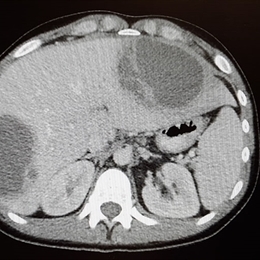

Zatürre, akciğerlerdeki hava keselerinin enflamasyonuna neden olan ve solunum yoluyla bulaşan bir alt solunum yolu / akciğer enfeksiyonudur. Bu hastalıkta, hava kesecikleri sıvıyla dolar ve bu durum, balgamlı öksürüğe neden olur. Ayrıca, ateş, üşüme nöbetleri ve nefes almada güçlük gibi belirtiler de balgamlı öksürüğe eşlik edebilir. Çeşitli bakteri, mantar ve virüslerden kaynaklanabilen zatürre, tedavi edilmediği takdirde hem çocuklar hem de 65 yaş üzeri yetişkinlerde ciddi sonuçlar doğurabilir ve hatta ölümcül olabilir.

Hastalığın şiddetine göre, belirtiler hafif veya ağır seyredebilir. Bu durum, ayrıca, hastalığın akciğerin tek lobunda mı yoksa iki lobunda da mı görüldüğüne göre değişir. Bakteri kaynaklı zatürre, bir üst solunum yolu enfeksiyonuna bağlı olarak gelişebilir. Aynı zamanda, kronik hastalığı olan kişilerde mantar kaynaklı zatürre de görülebilir. Özellikle mantar kaynaklı zatürrenin görülme sıklığı, coğrafi bölgeye göre değişiklik gösterebilir.